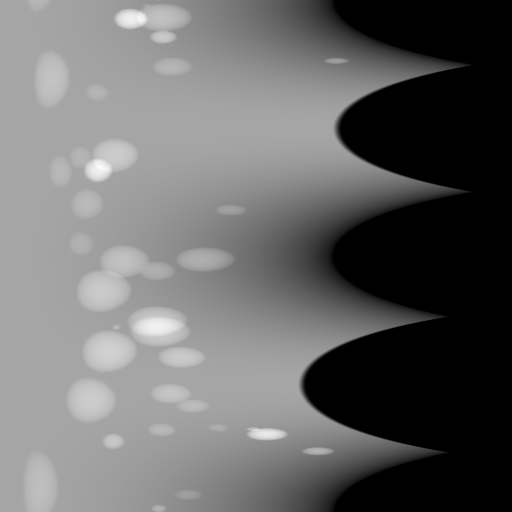

The complementary view setting for learning perspective deformation is also evaluated on real CBCT projection data. In this evaluation, real CBCT projection data from a dataset of knees with metal implants is used for testing, while DRRs created from volumetric CT datasets with inserted metals is used for training. Three exemplary DRR perspective projection images for training are displayed in Fig. 13, in which synthetic metal implants are inserted [34]. The appearance, e.g., image contrast and metal image resolution, of such DRR training images is different from that of real projection images in Fig. 14. In Fig. 14, the results for three knees, with and without metal implants, are displayed. The first and second rows are the 0superscript00^{\circ} and 180superscript180180^{\circ} perspective projections, respectively, rebinned to the virtual detector with geometric calibration based on their respective principal points and projections of the world origin. The third row displays their difference images, where the magnitude of deviation increases from the center towards the outside like it does in DRRs with an ideal scan trajectory (e.g., Fig. 6(e)), although real projection data suffer from various physical effects like beam hardening and Poisson noise. The fourth row displays the RGB stacks of 0superscript00^{\circ} and 180superscript180180^{\circ} perspective projection images. The magenta and green regions indicate structures with considerable perspective deformation, for example, the knee patella in Fig. 5.4, the top parts of the two metals in Fig. 5.4, and the bottom two screws in Fig. 5.4. The fifth row displays reference images, which are orthogonal projections of iterative reconstruction volumes from measured CBCT projection data. In the reference images, a total of five landmarks are selected, with the positions being marked by the green dots: In Fig. 5.4, two positions at the edges of the knee patella are marked; In Fig. 14(e) and Fig. 14(f), one position at the left edge of the fibula is marked for each image. In addition, a rectangular frame for the two metals is marked by the green dashed lines, while its width and height are indicated by the green solid lines, which are 29.71 mm and 111.99 mm, respectively. In Fig. 14(f), the centerlines of the bottom two screws are sketched by the green lines, which have the lengths of 17.14 mm (middle screw) and 19.38 mm (bottom screw). The corresponding rectangular frame for the two metals and the screw centerlines in the perspective projection images are marked as well, but in red color. In Fig. 14(a), the width and height of the metals are 32.56 mm and 109.85 mm, which have deviations of 2.84 mm and -1.95 mm to the reference ones, respectively. In Fig. 14(b), the centerline lengths are 18.91 mm and 19.54 mm, which have deviations of 1.77 mm and 0.16 mm, respectively. Although the bottom screw has little length deviation to the reference, the orientations of both screws are obviously deviated. The sixth row shows the results of Pix2pixGAN using 0superscript00^{\circ} and 180superscript180180^{\circ} polar inputs. For all of the landmarks, the green reference dots are all located accurately in the Pix2pixGAN images. The rectangular reference frame also accurately covers the metals in Fig. 14(g). In Fig. 14(h), although the two red centerlines do not exactly overlap with the green one, they are very close in lengths and orientations. Please zoom in for better visualization.

In the real cadaver data, certain metal implants are distorted in Pix2pixGAN predictions. For example, the long metal rod indicated by the red arrow is no longer straight in Fig. 18(c), although its position is between the corresponding magenta and green rods in Fig. 18(b). Another limitation is that certain structures like thin K-wires from 0superscript00^{\circ} and 180superscript180180^{\circ} perspective projection images will remain as shadows in the Pix2pixGAN prediction, for example, those indicated by the blue arrows in Fig. 18(c).